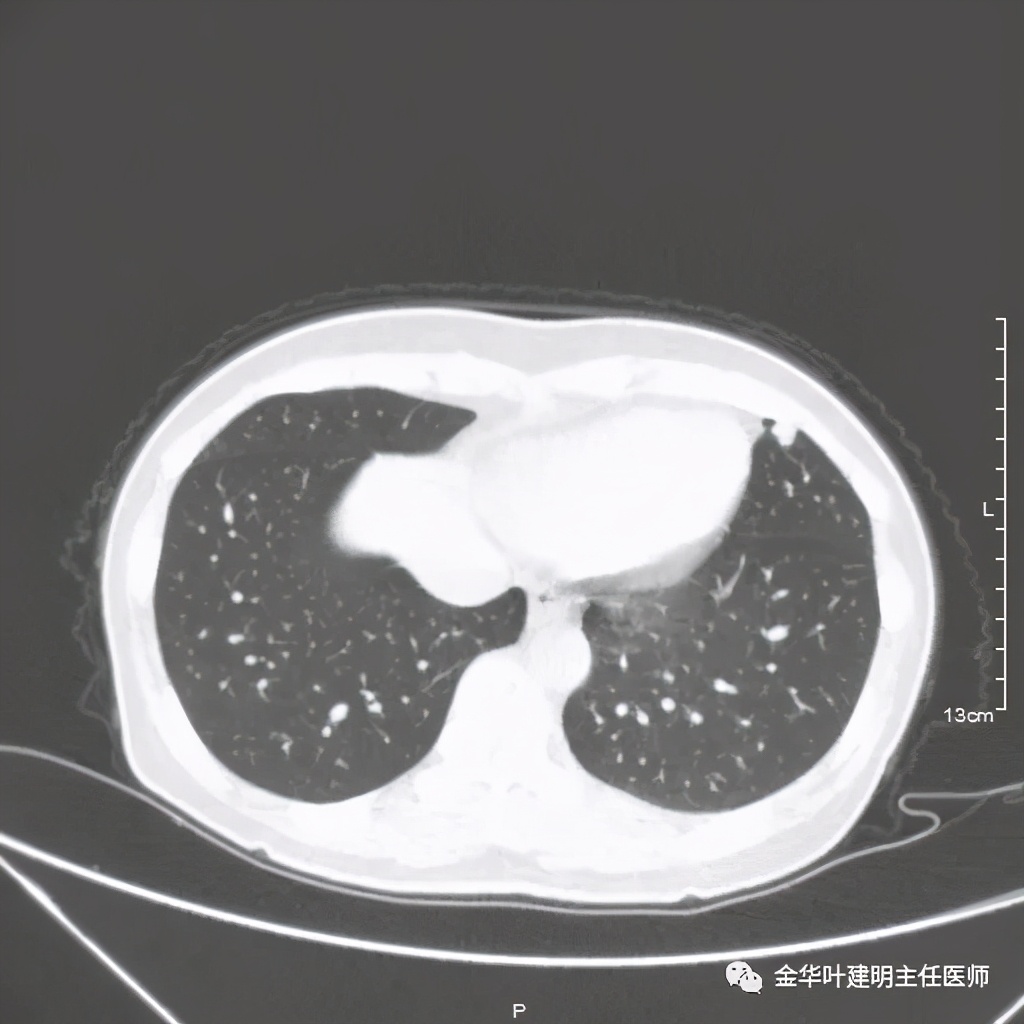

六、神经内分泌癌(此例为不典型类癌,小细胞癌以后再总结):

影像特征:不典型类癌一般圆形生长,实性,边缘比较光滑,但硬度不够。侵蚀力也不够。就像这例,我们发现其与肺动脉接触的地方,居然无法推压血管,反而肿瘤被血管占据了其生长的位置,在支气管内,肿瘤也是对支气管壁没有造成明显的破坏。也就是说 圆形边清较软、侵蚀力弱的实性结节 要考虑类癌的可能性。